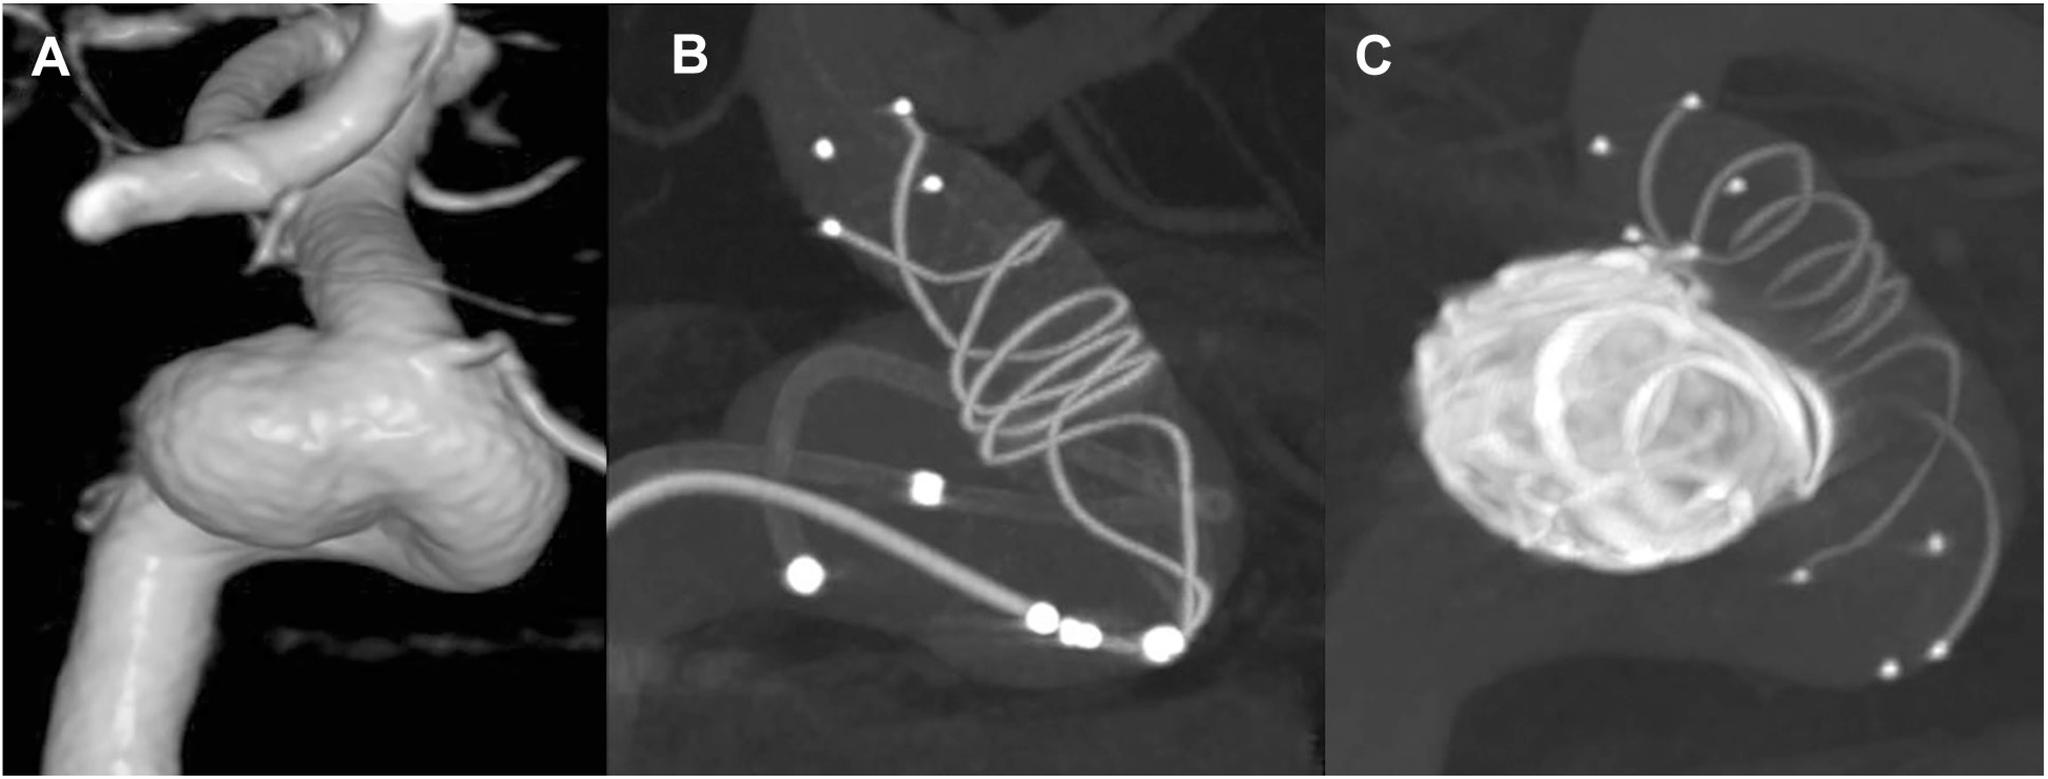

There have been no delayed ischemic complications related to stent-assisted coil embolization (SACE) of cerebral aneurysms at our institution. We demonstrate our strategies for stent placement and postoperative management of antiplatelet therapy to reduce the risk of ischemic complications.

We analyzed 57 cases of SACE retrospectively. In the procedure, an appropriate stent was selected and placed to fit the arterial wall without impeding on small arterial branches. Two different antiplatelet drugs, including clopidogrel, were used. Six to twelve months after surgery, follow-up angiography was performed to assess the safety of terminating antiplatelet therapy. In cases in which antiplatelet therapy was tapered, the two antiplatelet drugs were switched to clopidogrel alone, and it was subsequently tapered and finally discontinued.